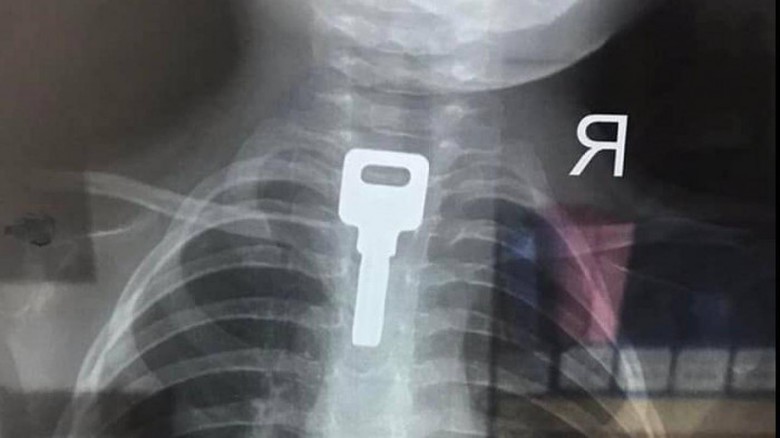

BV Nhi Đồng 2 TP.HCM thông tin, các bác sĩ nơi đây vừa phẫu thuật lấy dị vật là chìa khóa kim loại trong thực quản bé trai 2 tuổi. Chìa khóa có kích thước 2x4cm.

Dị vật là chìa khóa được phát hiện trên film chụp tại BV Nhi đồng 2 TP.HCM

Gia đình cho biết, thời điểm đó chìa khóa đang cắm trong ổ, bé đã tự lấy xuống chơi. Thấy cháu cho vào miệng ngậm, người nhà vôi can ngăn nhưng bé hốt hoảng đã nuốt luôn chìa khóa.

Sau khi nỗ lực dùng tay lấy ra nhưng bất thành, bé nhanh chóng được gia đình mang đến bệnh viện. Qua kiểm tra phát hiện dị vật ở thực quản, bé đã được các bác sĩ khẩn trương lấy ra thành công.